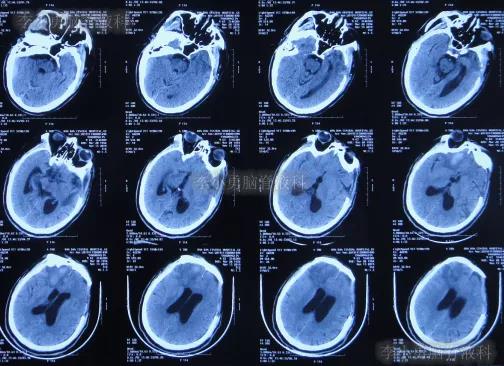

2019年10月20日患者骑电动车在马路上行驶时被大货车撞倒,当时意识清楚,只感到有些头晕,未在意就自行回家,但回家后约3-4小时出现头晕加重,并伴有恶心呕吐的症状,家人急送到当地的河北省邯郸市某医院,查头颅CT示脑出血(图-1);既往病史2015年曾因头部外伤致硬膜下血肿,进行了钻孔引流术。

图-1:2019年10月20日头颅CT